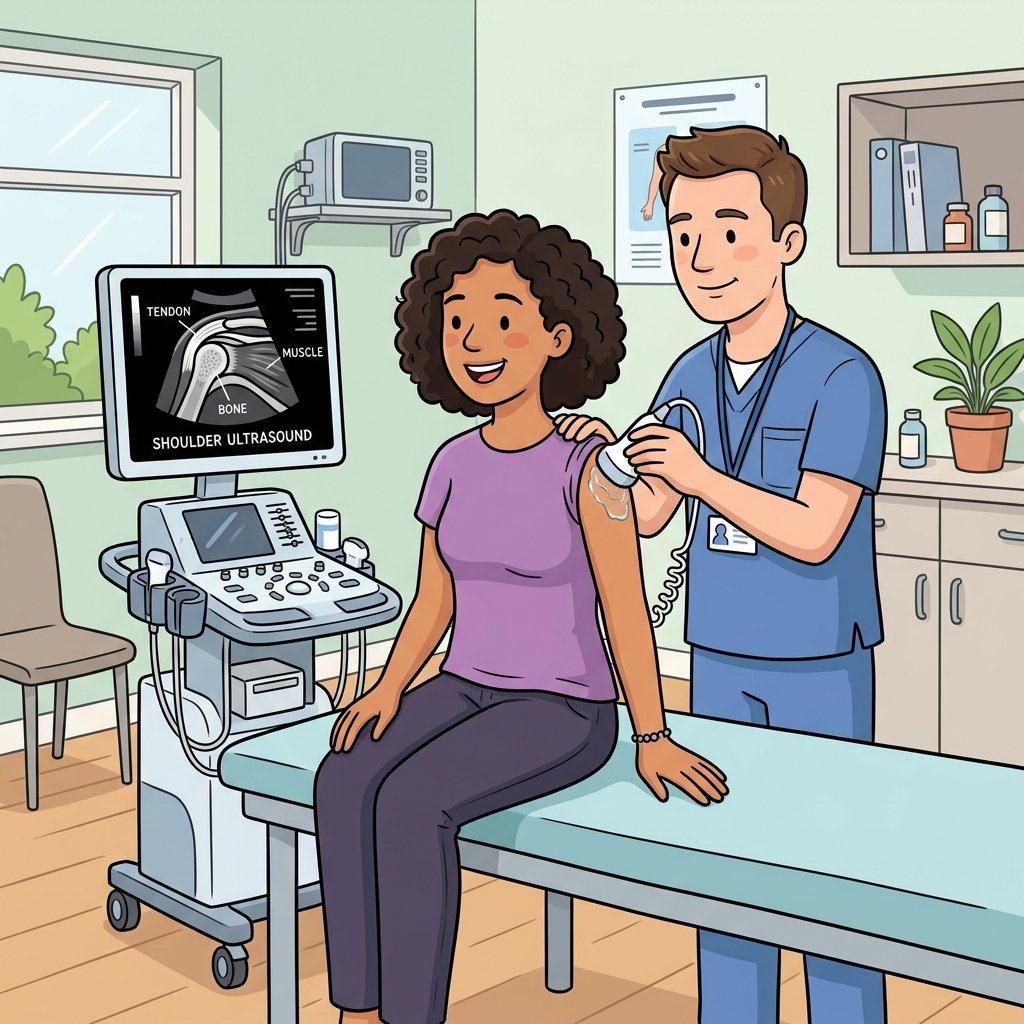

1 Essential Shoulder Ultrasound Scan London Guide

Shoulder ultrasound scan London specialists use one of the most powerful and versatile diagnostic tools available for shoulder pain. Unlike...